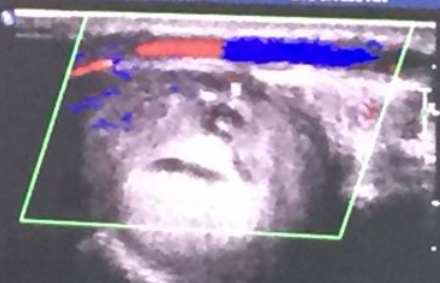

血液透析血管通路的建立与维护:科室拥有血管通路医护团队,设有血管通路专病门诊,多学科协同术前彩色多普勒血管超声检查、术中超声引导以及术后通路超声复查、复杂血管通路及中心静脉的CT血管成像(CTA)和数字减影血管造影(DSA),可开展经皮B超引导下内瘘血管腔内成形术(PTA)、肢体静脉动脉内瘘手术、中心静脉血透导管置入术以及DSA下中心静脉狭窄球囊扩张后建立血透导管等疑难复杂通路的问题。

(3)B超引导下经皮腔内血管成形术(PTA):

图 超声引导下PTA球囊封堵治疗假性动脉瘤术前后对比